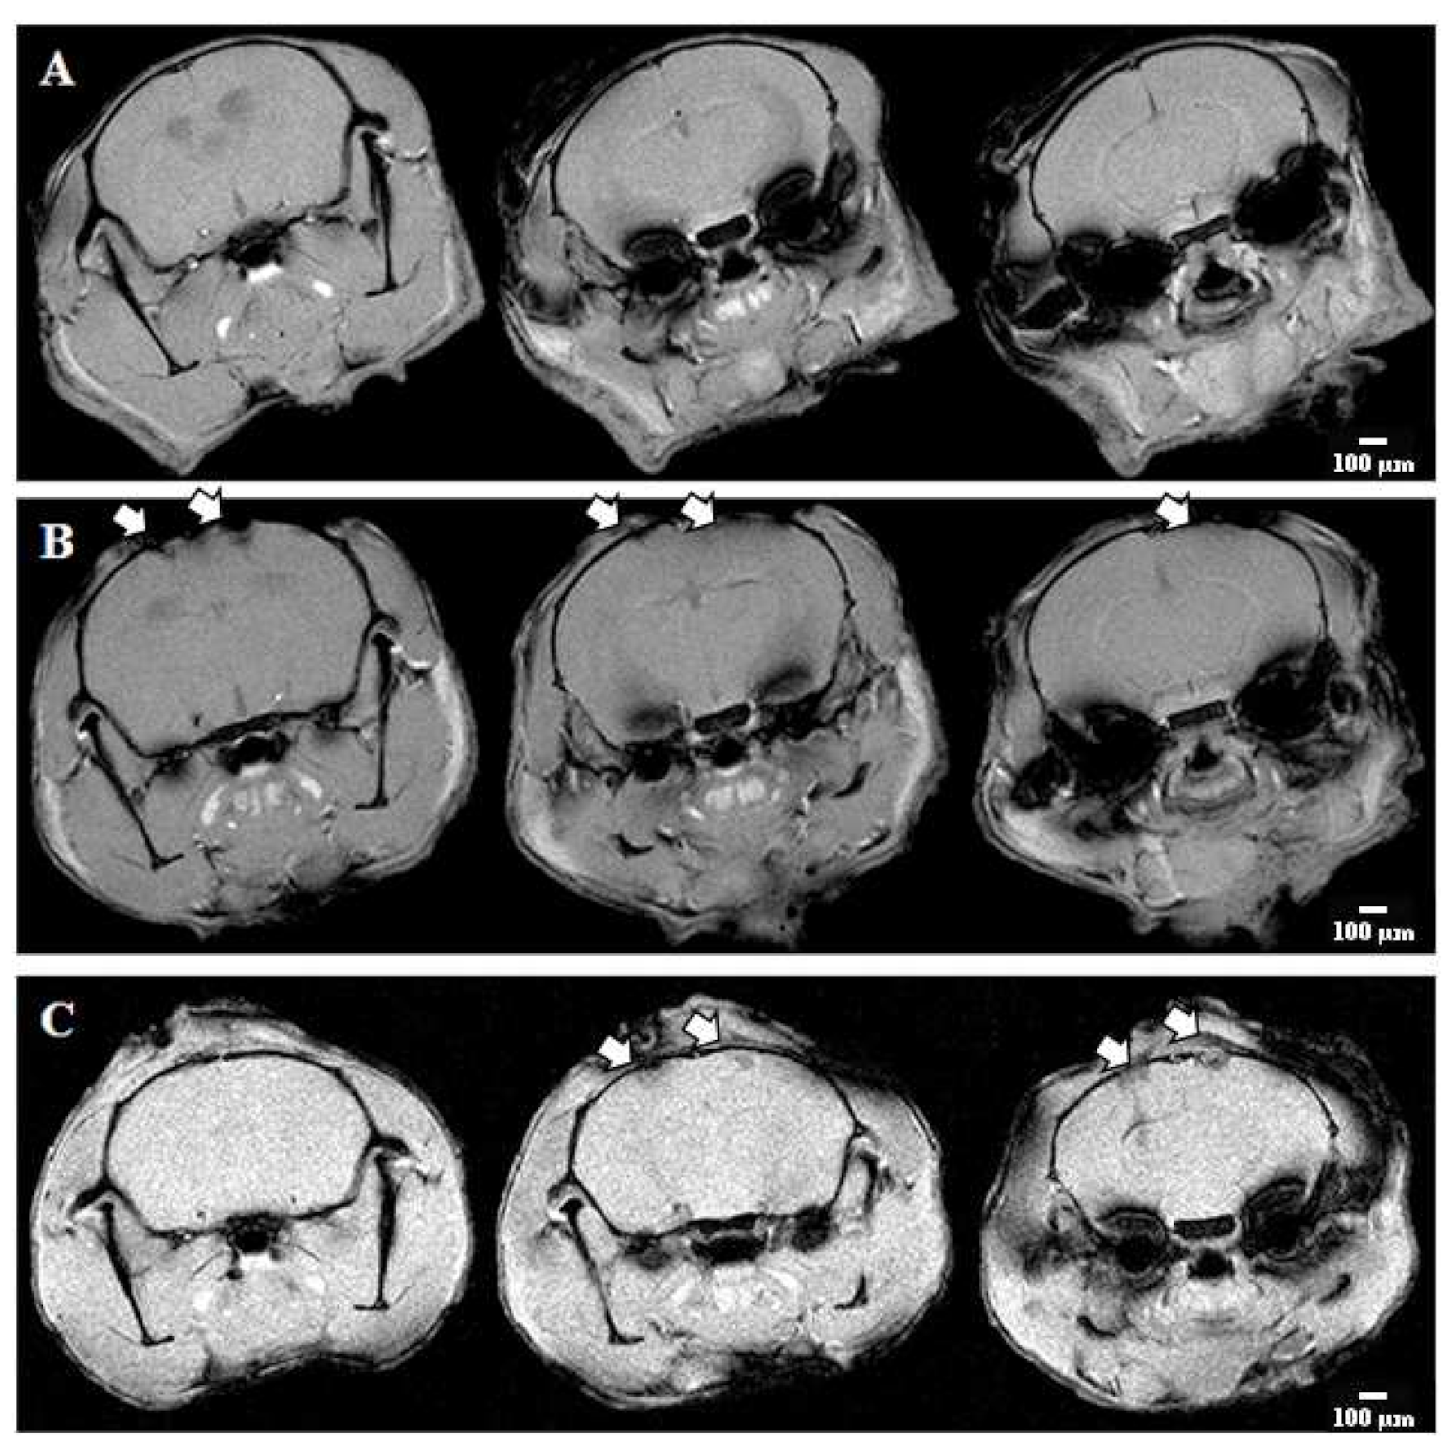

4.13. Magnetic Resonance Imaging

2.3. Histopathological Evaluation